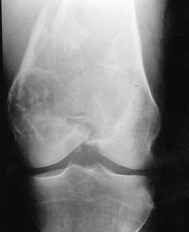

X-ray

Multi-loculated expansile lesion with cortical thickening

Often fail to make definitive diagnosis on xray